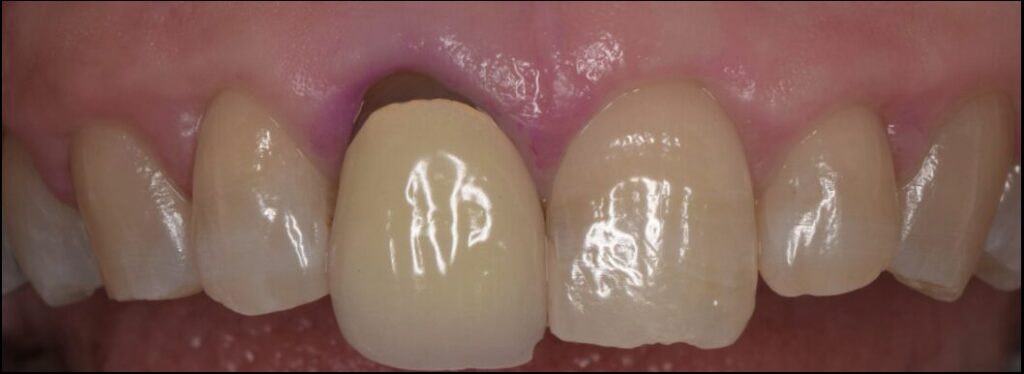

Before